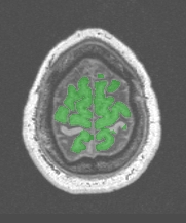

Correction Brain Mask from T1 MRI

For some reason, the procedure Brain Mask From T1 MRI failed for one of your images. A solution may be provided by this procedure, which proposes variants of the standard one. You can choose one of these variants in the menu. After applying this treatment, the result can be visualized in Anatomist if you select Mask visualization.